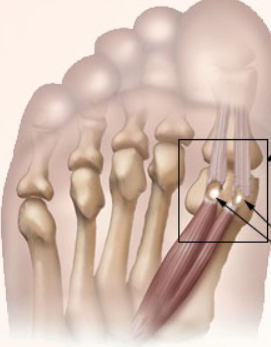

Morton’s Neuroma: A Complete Guide to Symptoms, Diagnosis, and Treatment

Morton’s neuroma is a common cause of forefoot pain. Learn the real symptoms, the tests that matter, when ultrasound helps, the shoe features that reduce pressure, how to place a met pad, and when surgery makes sense.